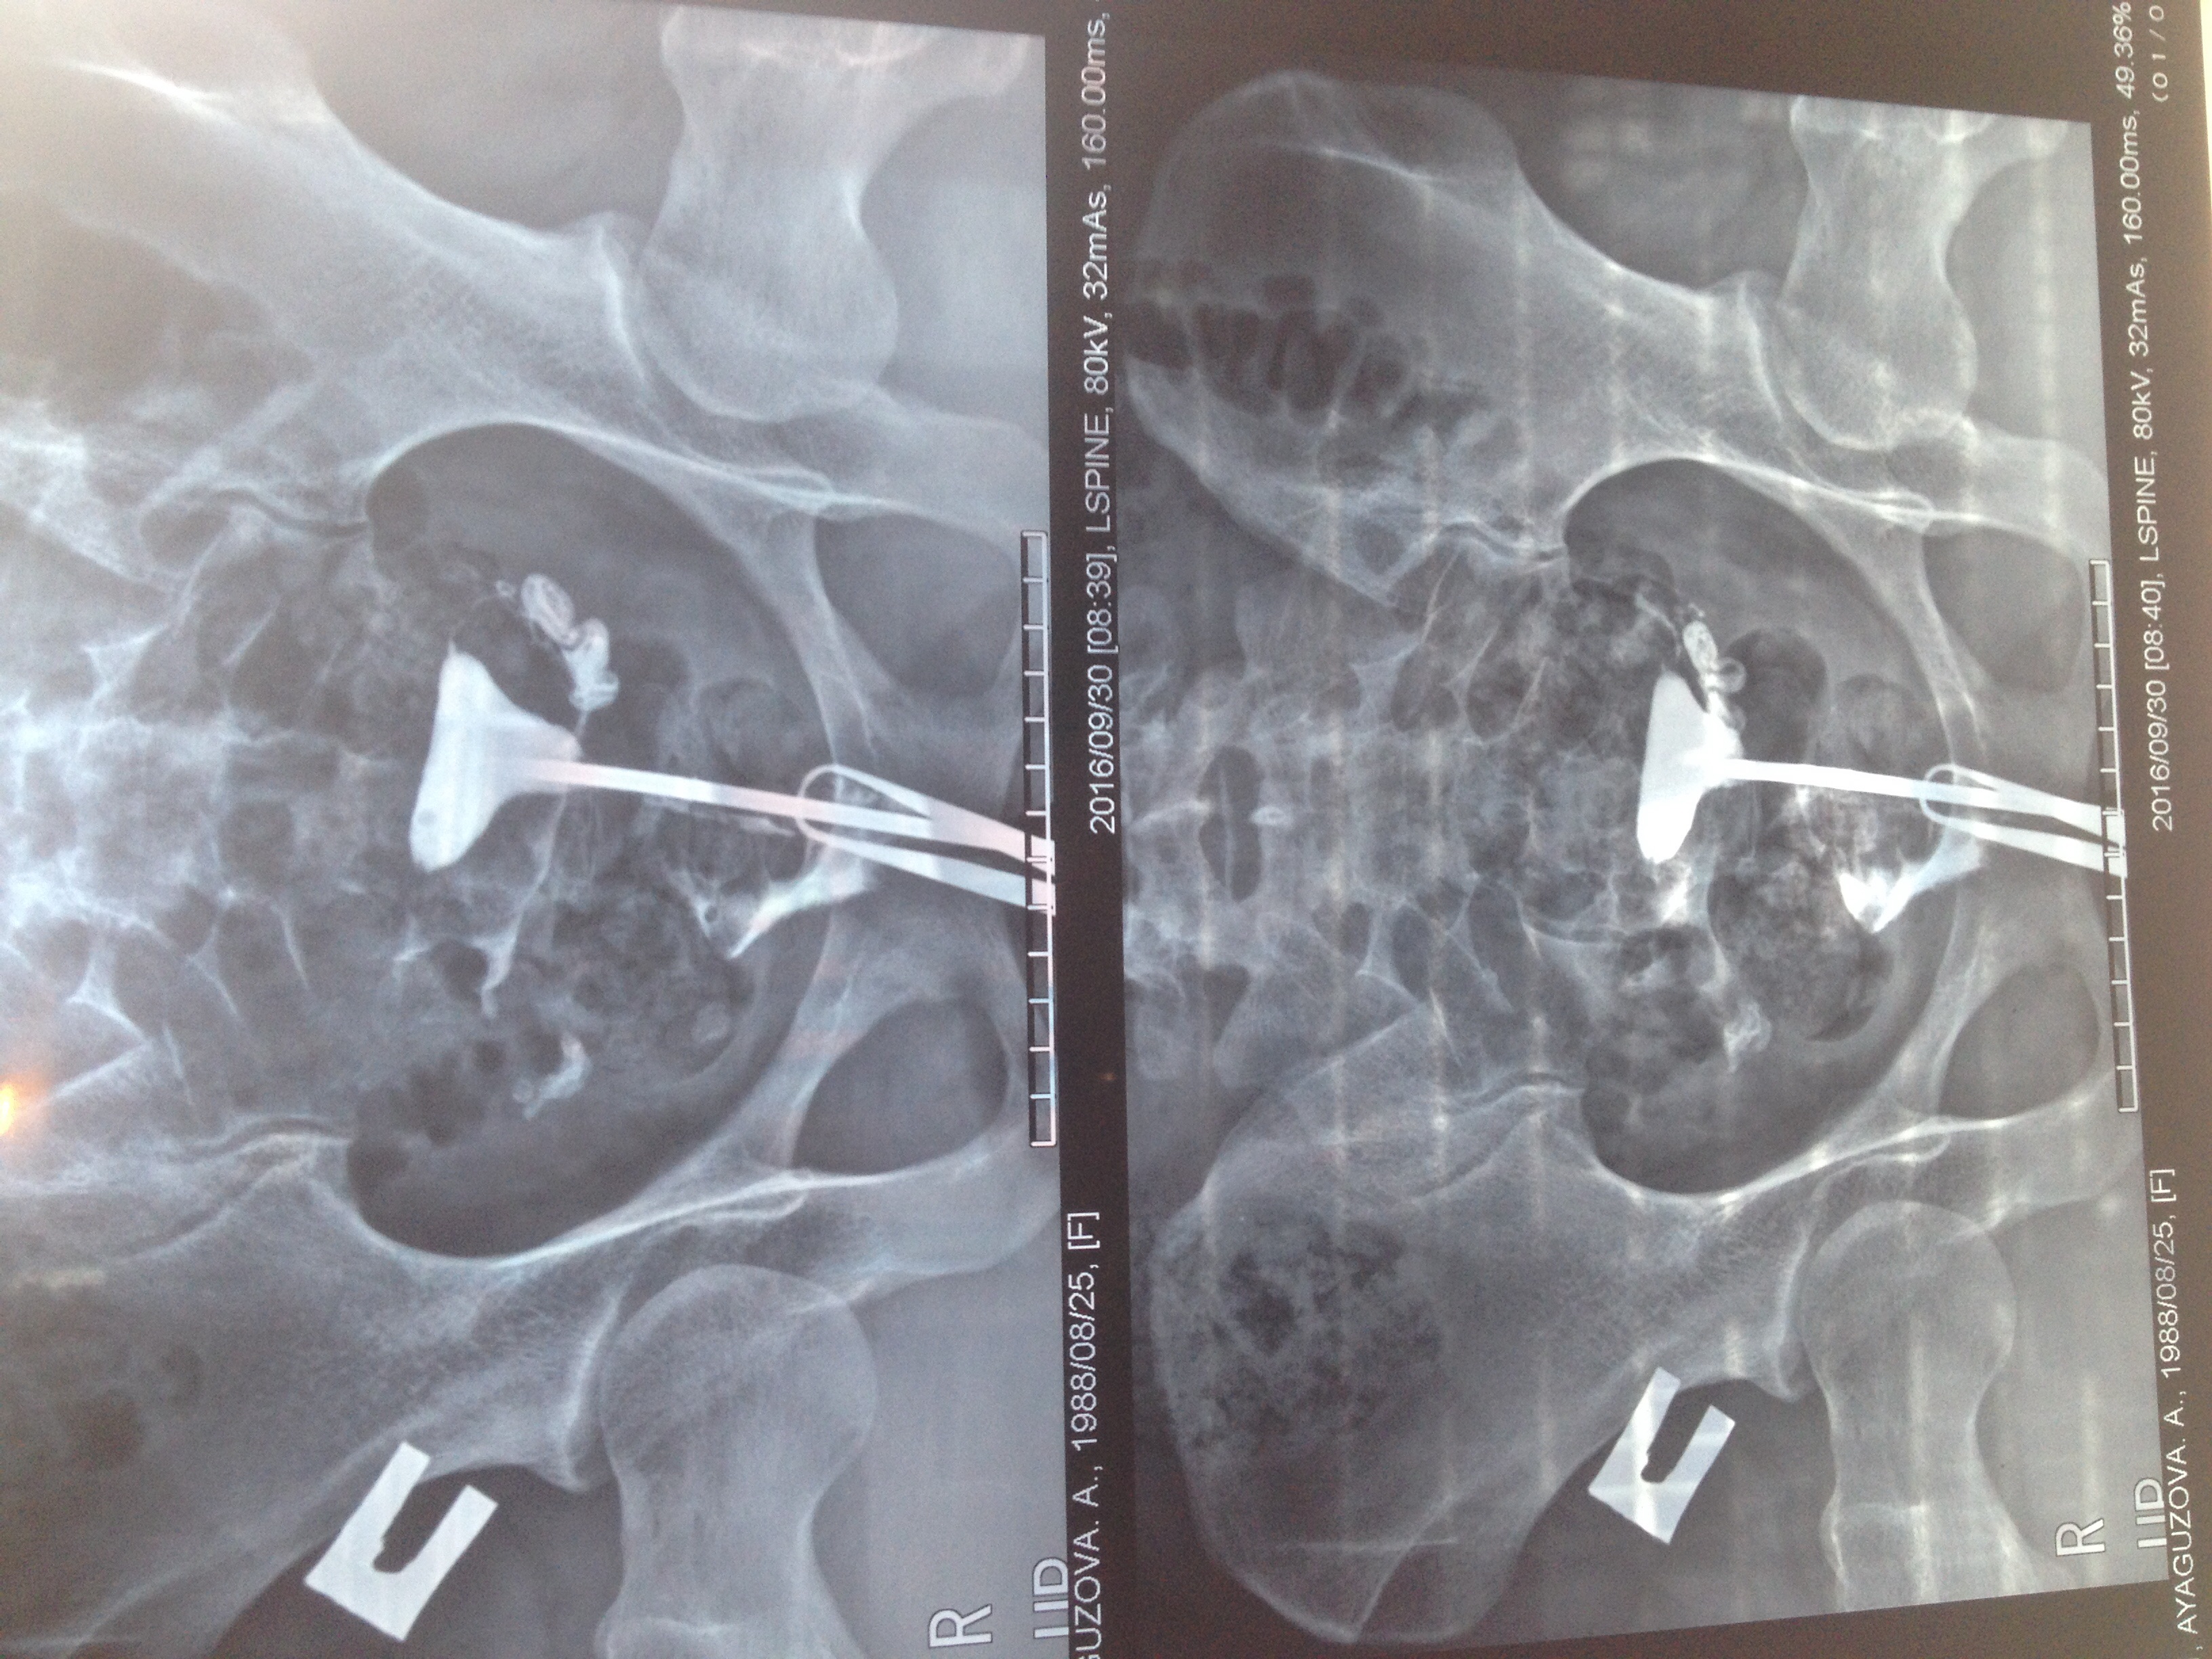

Медицинские снимки: Проходимость маточных труб